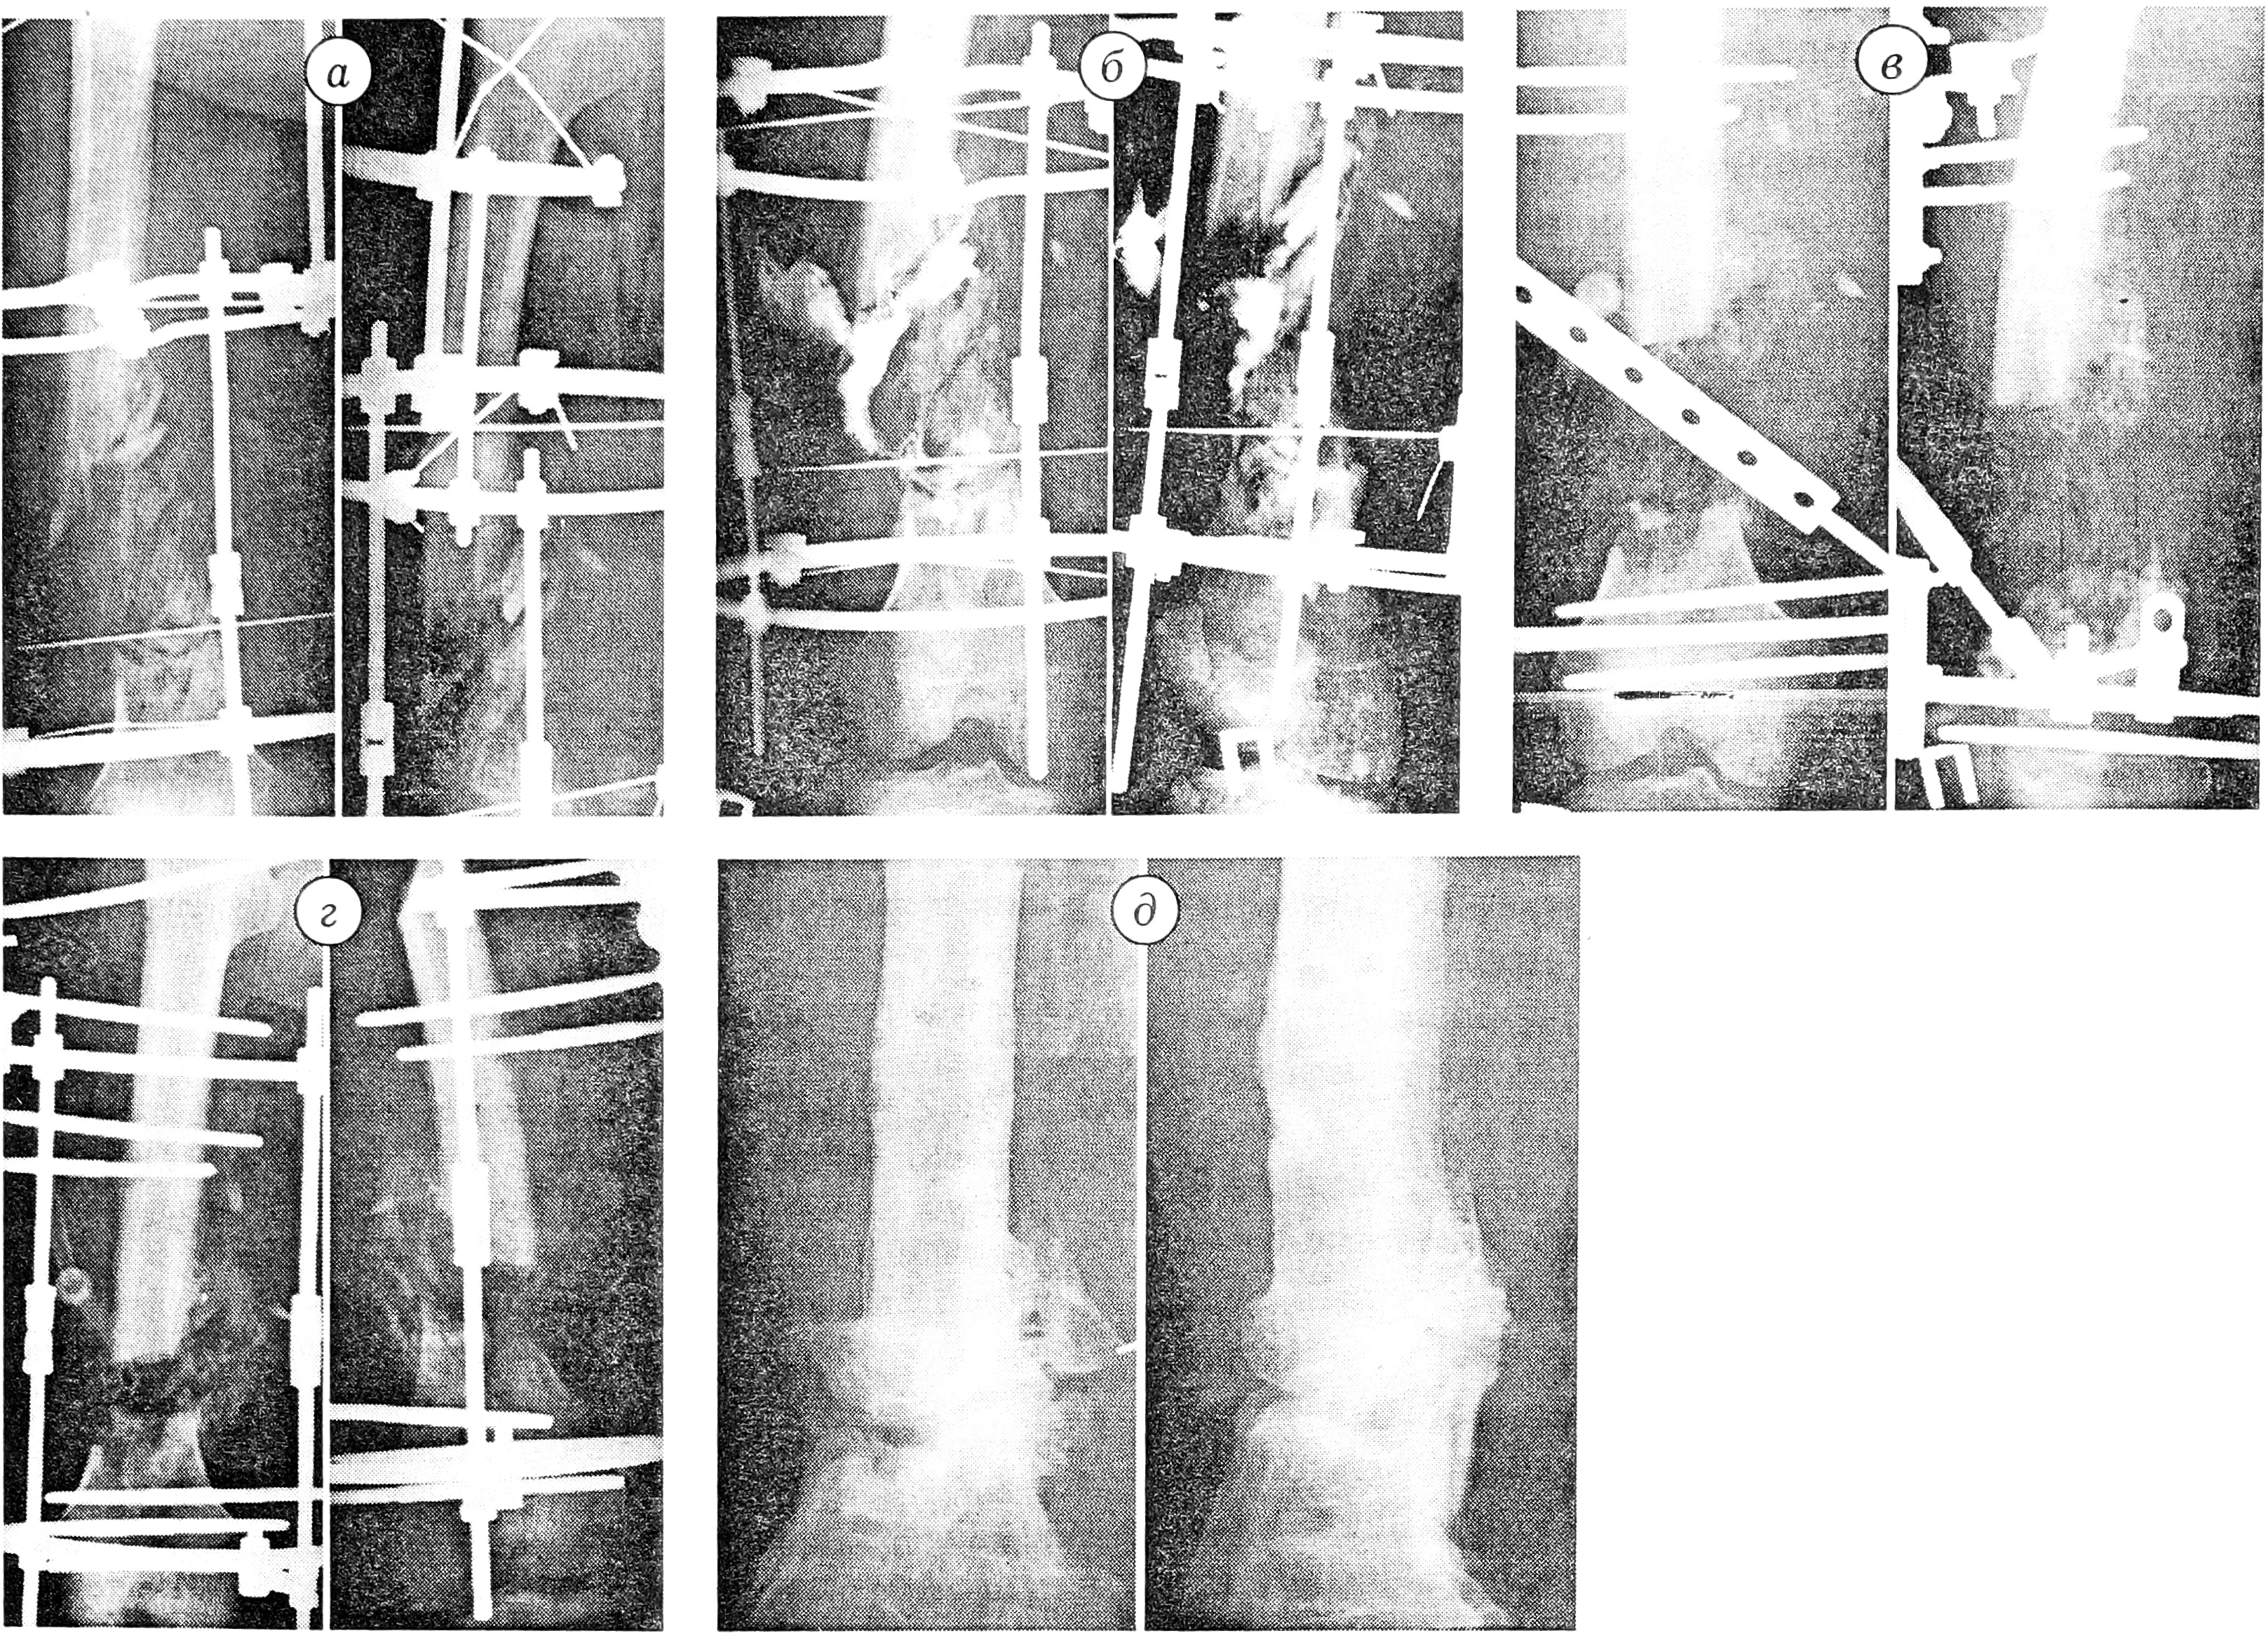

На рентгенограммах и фистулограммах: обширный остеомиелитический процесс в нижней трети правого бедра в области огнестрельного повреждения (рис. 3, а); спица от аппарата Илизарова проходит через очаг поражения; контрастное вещество проникает в область огнестрельного перелома (рис. 3, б). Из отделяемого свища выделена ассоциация микроорганизмов — Proteus vulgaris, Clostridium и др., чувствительная к цефтазидиму, ципрофлоксацину, устойчивая к ампициллину, гентамицину, доксициклину, левомицетину, полимиксину, тобрамицину.

Рис. 3. Больной 3. 60 лет с хроническим огнестрельным остеомиелитом нижней трети правой бедренной кости.

а — рентгенограммы, б — фистулограммы правого бедра при поступлении; в — рентгенограммы после резекционной секвестрнекрэктомии и чрескостного остеосинтеза стержневым аппаратом; г — в процессе лечения; д — после снятия стержневого аппарата: остеомиелит ликвидирован, достигнуто сращение.

После предоперационной подготовки произведена операция: демонтаж аппарата Илизарова, резекционная секвестрнекрэктомия, остеосинтез стержневым аппаратом. Рана дренирована. В образовавшийся дефект протяженностью 11,5 см имплантирован коллапан с антибиотиком в соответствии с данными антибиотикограммы (рис. 3, в).

В послеоперационном периоде отломки постепенно сближены до достижения контакта (рис. 3, г). Рана дренировалась, частично зажила вторичным натяжением. Аппарат снят через 14 мес (рис. 3, д). Перелом сросся, остеомиелит был ликвидирован. Больной осмотрен через 18 мес: ходит без дополнительных средств опоры с полной нагрузкой на оперированную конечность, укорочение компенсировано ортопедической обувью.